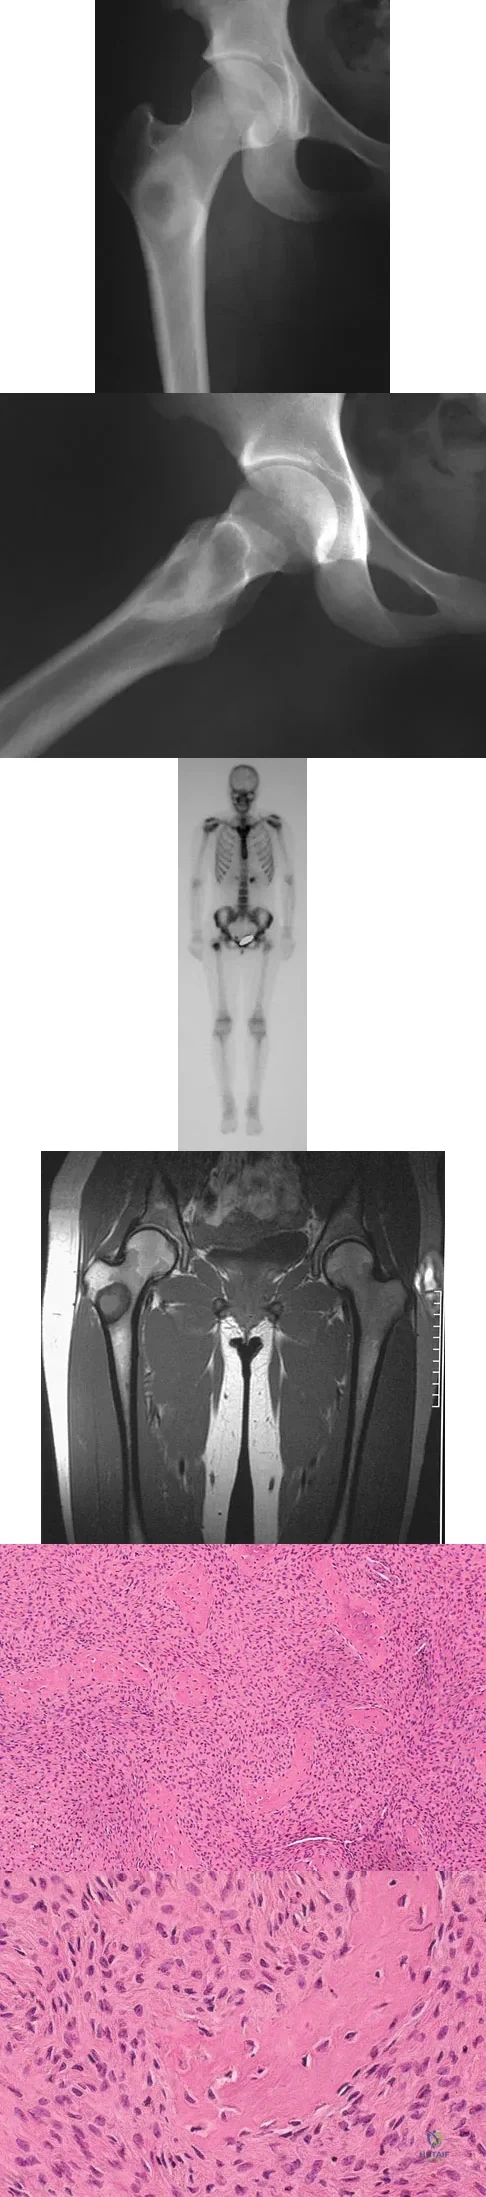

A 16-year-old girl injured her hip in a fall. Radiographs are shown in Figures 14a and 14b. She denies any history of pain prior to the fall and is currently asymptomatic. A bone scan, MRI scan, and biopsy specimens are shown in Figures 14c through 14f. What is the most likely diagnosis?

Explanation

Although the classic radiographic appearance of fibrous dysplasia is one of a central metaphyseal lesion with ground glass matrix, it is not unusual to see either a more radiodense-appearing lesion or a more peripheral location. The histologic finding of spicules of woven bone without osteoblastic rimming in a bland fibrous background is diagnostic of fibrous dysplasia. The imaging studies could be consistent with low-grade osteosarcoma, osteoblastoma, or osteomyelitis, but all have a very different histologic picture. Observation is indicated in the absence of symptoms, impending fracture, or deformity. Fibrous dysplasia most commonly occurs in the proximal femur. Huvos AG: Bone Tumors: Diagnosis, Treatment, and Prognosis. Philadelphia, PA, WB Saunders, 1991, pp 30-43.